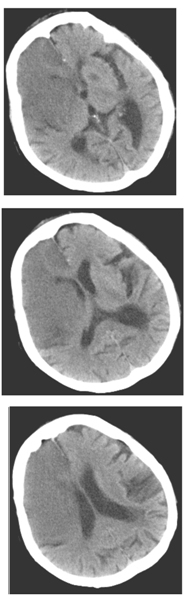

女性,70岁,昏迷,大小便失禁12小时。查体:血压200/110mmHg,心率约120次/分,体温37℃。浅昏迷,左侧肢体未见自主活动,肌力增高,Babinski征阳性。既往高血压病史。

6.患者检查图像如下,应考虑何种疾病

A.脑膜炎

B.星性细胞瘤

C.脑出血

D.脑动静脉畸形

E.脑梗塞

F.脑脓肿

7.诊断依据是哪些

A.昏迷,大小便失禁12小时

B.CT显示右侧大脑额、颞叶大片状均匀低密度灶

C.既往高血压病史

D.右侧侧脑室受压

E.大脑镰钙化

F.左侧基底节区低密度灶

8.大面积脑梗塞的典型表现包括

A.梗塞区域与该区动脉供血区域一致,呈扇形或楔形,同时累及灰质和白质

B.梗塞发生6h后,可见大脑中动脉水平段条形高密度影,外囊与岛叶皮层界限模糊

C.梗塞区脑沟变浅

D.6~24小时部分病灶出现低密度

E.大部分病例24h之后才出现典型的低密度改变

F.增强后病变明显强化